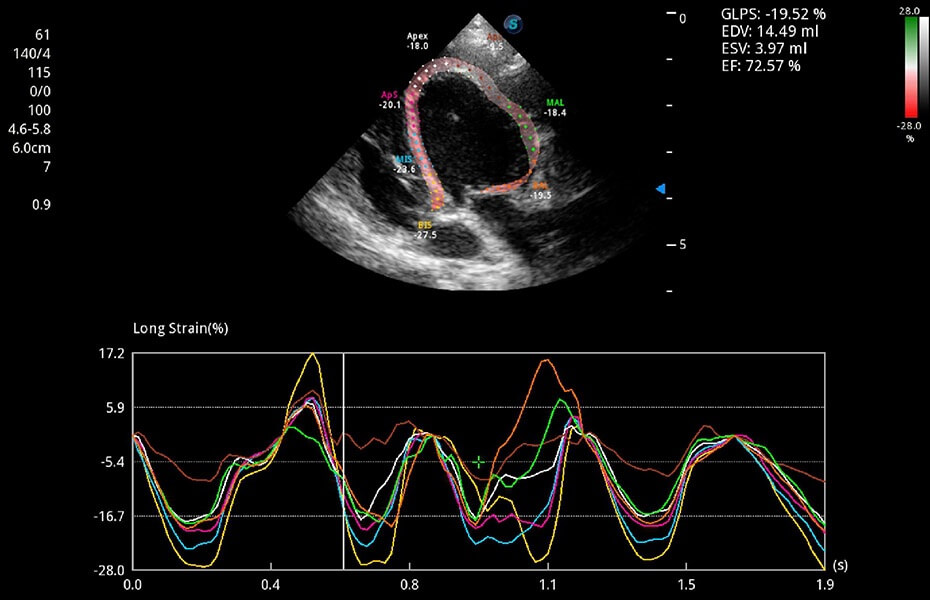

ProPet 60 作為一款高端臺式動物超聲設備,為動物醫(yī)生的日常診斷提供了一系列貼合動物臨床需求、解決臨床實際問題的高級成像功能。憑借全系列高清探頭,滿足醫(yī)生對腹部、心臟、生殖、淺表、肌骨等成像的所有需求,切實幫助您提升檢查效率,提高診斷信心。